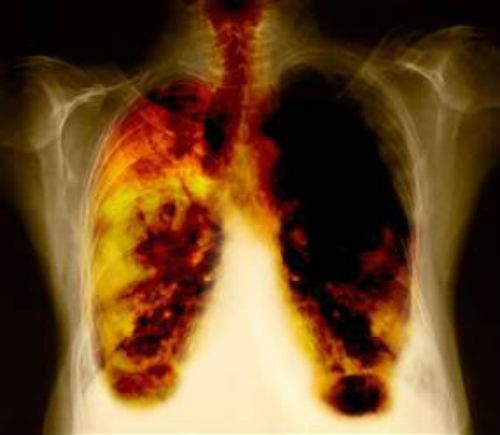

Hình ảnh ung thư phổi do hít khói bụi, bồ hóng. |